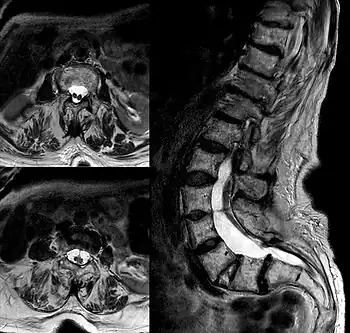

| Diastematomelia in MRI of lumbar spine. | |